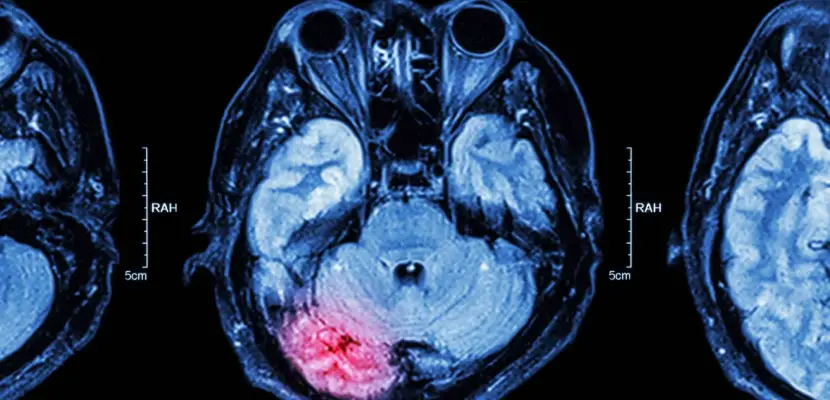

A traumatic brain injury occurs when there’s sudden brain trauma. Depending on the level and intensity of the injury, a head injury can lead to memory loss, emotional and mood issues, slurred speech, personality changes, confusion, disorientation and serious headaches. Unlike other physical injuries, TBIs, particularly in moderate cases, may not always show until after a few hours or even days following an accident. For that reason, it is critical that you seek medical attention immediately after an accident in order to establish whether you have suffered a head injury. Beginning treatment as soon as the accident occurs gives you the best chance for a full

recovery.